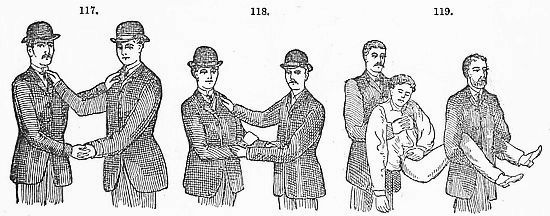

The Sickroom.—The Room; the Nurse; the Bed; Sickroom Accessories; Feeding Patients; Invalid Dishes and Drinks; Administering Physic; Domestic Remedies; Accidents and Emergencies; Bandaging; Burns; Carrying Injured Persons; Wounds; Drowning; Fits; Frostbites; Poisons and Antidotes; Sunstroke; Common Complaints; Disinfection, &c.